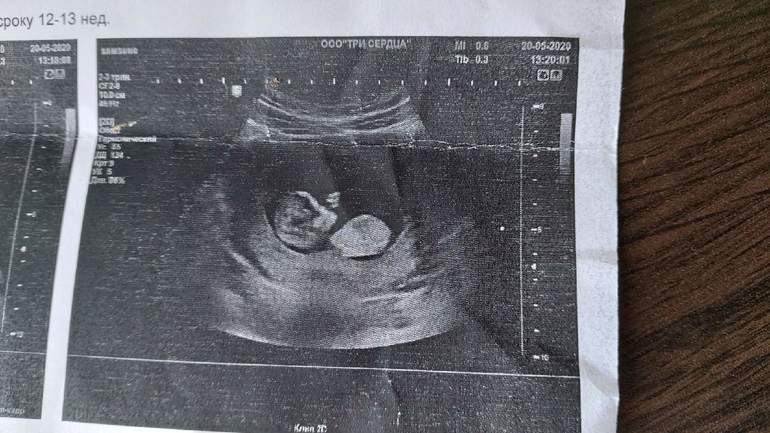

узи, кого видите?

Пол малышаНашла узи, кого видите? На кого похоже?😁

Узист мальчика увидел, я все кручу верчу снимки мне вообще ничего не видно😁Говорят они как то по углу предполагают

Ну по первому фото мне кажется 100% девочка. У меня у дочки даже больше вверх бугорок торчал в 15 недель

На самом первом фото бугорок под углом,похож на мальчишеский...А дальше просто может так сделано фото)Но на таком сроке,если узист не опытный,то могут быть ошибки,конечно.У мальчиков обычно просто более выраженный угол вверх...

Больше похоже на девочку. Хотя небольшой угол отклонения как будто есть, но совсем мало

У мальчиков обычно сильнее задран бугорок. На этом фото похоже на девочку. Недели через 2 будет уже хорошо видно, если пацан

На девочку очень похоже, где ваш Узист мальчика увидел🤔найду фото покажу как мальчики выглядят.